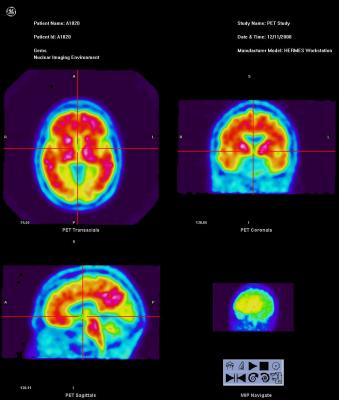

Vizamyl (flutemetamol F-18) scan of a brain of an Alzheimer's patient.

October 25, 2013 — The U.S. Food and Drug Administration (FDA) today approved Vizamyl (flutemetamol F 18 injection), a radiopharmaceutical tracer, for use with positron emission tomography (PET) imaging of the brain in adults being evaluated for Alzheimer's disease (AD) and dementia. The agent was developed for GE Healthcare by Medi-Physics Inc.